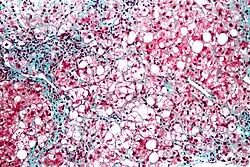

- Hepatic steatosis, or fatty liver disease (FLD), is largely researched because it is closely connected to obesity and metabolic syndromes. Hepatic steatosis is caused by the deposition of triacylglycerols (TG) in the cytoplasm of the hepatocyte. This can cause inflammation of the cells, cell death and fibrosis (steatohepatitis).

In a mouse model, hepatic steatosis is a survival strategy when in a starved state for 24 hours, but in humans hepatic steatosis can lead to fattening of the liver. The main question in this area of research is the comprehension of the shift from a survival strategy to the occurrence of pathogenesis such as steatohepatitis. To understand this, it is important to discover how the concentration of lipid compounds in the liver changes after a period of starvation. High performance thin-layer chromatography (HPTLC) and reversed phase liquid chromatography coupled to mass spectrometry (LC-MS) were used to quantify and qualify the changes in lipid compounds in the liver.

Large increases in 44:2-TG and 48:3-TG were seen in liver tissue after starvation when they are normally found in adipose tissue. This suggests that there is a transfer of lipids from adipose to liver tissue when carbohydrates concentrations are low. There was also a significant rise of hepatic free cholesterol and cholesterol esters after starvation. Cholesterol has an important role in membrane fluidity, so it is possible that starvation will have negative effects on the fluidity of the liver cell membranes. Also, after starvation, a 49:4-TG was observed in liver homogenate from the mice that was not seen in the control group. This TG with an odd number of carbon atoms can be used as a new biomarker for starvation-induced hepatic steatosis.

In conclusion, this study used HPTLC and LC-MS to show that the liver is highly dynamic and has an essential role in response to fasting and conversions of metabolites in lipid metabolism. In the liver, there is repartitioning and turnover of free fatty acids which causes a buildup of triacylglycerols in hepatocytes (hepatic steatosis).